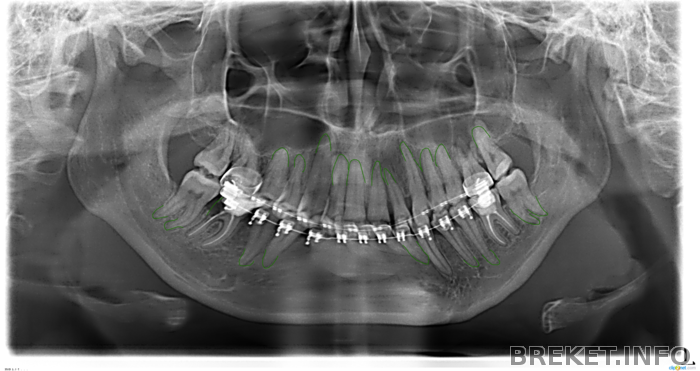

Где мои корни???

Халва, а почему корешки нижних резцов не видно?